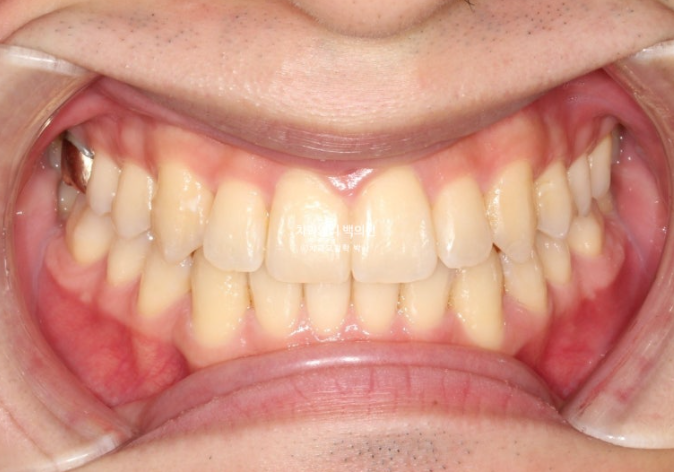

25.03

치료 후 중심선은 완벽하게 맞습니다.

뻗쳐있던 앞니와 송곳니가 개선이 되고 스마일라인이 정돈되었습니다.

앞니 기울기와 중심선이 개선이 되니 비대칭처럼 보이던 것도 해소가 되었습니다.